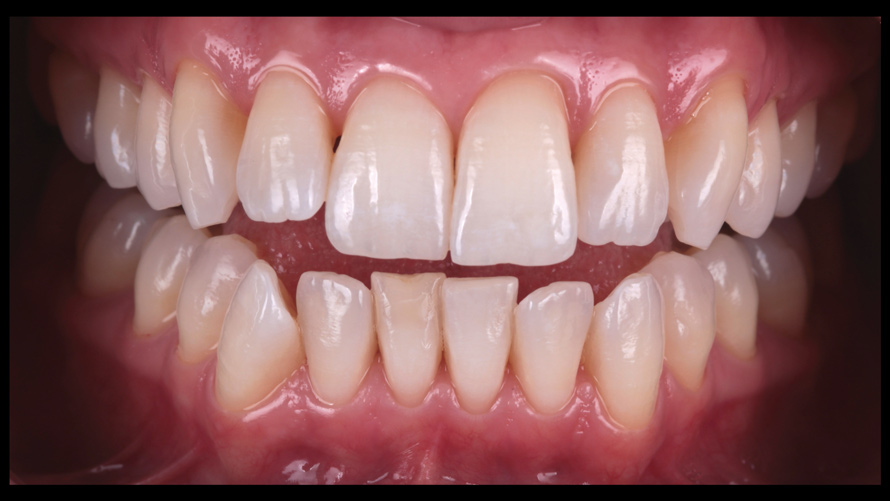

(9.) Preoperative esthetic case documentation using a smartphone and an EALS device.

Figure 9

(10.) Preoperative esthetic case documentation using a smartphone and an EALS device.

Figure 10

(11.) Preoperative esthetic case documentation using a smartphone and an EALS device.

Figure 11

One of the main advantages that smartphone cameras have over DSLR cameras is that nearly everyone is already very familiar with the technology; therefore, the incorporation of these devices into everyday practice does not require learning a new and unfamiliar skill set. The task of producing a series of high-quality clinical photographs for routine examinations (Figure 8), esthetic treatment planning (Figure 9 through Figure 11), or specialty care (Figure 12 and Figure 13) can be delegated with confidence to any staff member during the patient's initial office visit and will generally require less than 5 minutes of time to complete. When a DSLR camera is used, evaluation of the intraoral images either takes place on the small viewfinder built into the camera or necessitates the physical removal of the memory card from the camera to downloaded the images onto a computer for review. An added bonus of smartphone dental photography is that the phone's screen now replaces the much smaller viewfinder of a DSLR camera and provides the clinician with the ability to view and zoom into the patient images on a 5- to 6-inch, high-definition display.